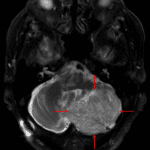

- Heterogeneous, nonenhancing mass in the left cerebellar hemisphere which is mildly T2 hyperintense relative to the adjacent cerebellar parenchyma

- Mild diffuse diffusion signal hyperintensity (largely representing T2 shine-through)

- Associated mass effect on the inferior aspect of the fourth ventricle

- Right cerebellopontine angle meningioma

Dysplastic cerebellar gangliocytoma (Lhermitte Duclos disease)